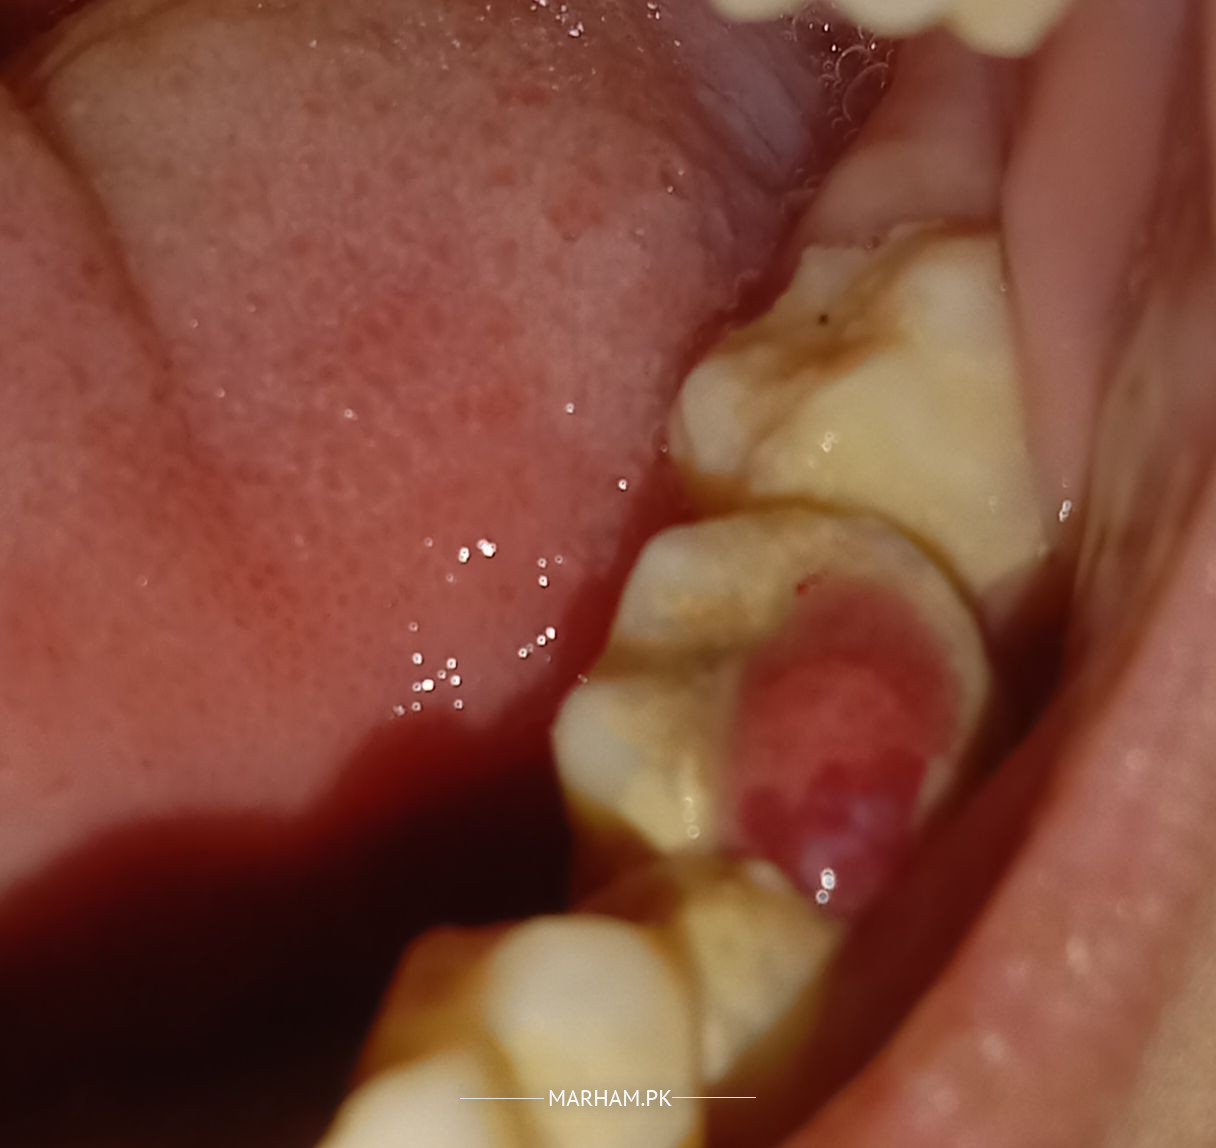

My Sister had this weird polp like maybe 2 months ago since then its constantly bleeding. recently it has stopped bleeding and there is white discharge of something, due to some problems we cannot go to a doctor, Please tell me if there is something to worry about or not? the picture is attached below. thank you have a good day.

it is pulp polyp. it result because of chronic necrosis. your sister's tooth is no more vital. there is no more treatment except extraction.

it's a urgent case . you have to visit a good dentist for this condition. for evaluation there is an periapical X ray will be required.. that white discharge is actually a pus . which is the result of severe infection in the roots of this tooth .. visit a dentist asap . or you can come to my clinic for her.

its a pulp polyp,it is due to necrosis of pulp, you should have xray and visit a dentist,asap . as it can damage neighboring teeth.

It is pulp polyp. Infection in roots of this tooth and white discharge is pus. Get an xray and visit your nearby dentist.